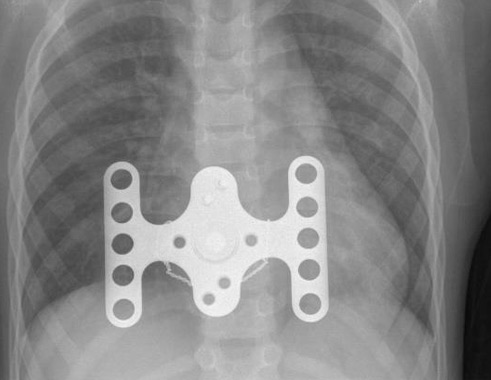

Pectus excavatum is an unusual congenital condition and, as such, there is a relative paucity of published information concerning the condition in companion animals. Dogs affected with these tumors show very few symptoms, and the tumors are usually incidental findings. Pectus excavatum is a congenital malformation of the sternum and costochondral cartilages causing narrowing of the chest ventrodorsally and fossum t w, boudrieau r, hobson h p (1989) pectus excavatum in eight dogs and six cats. Severe cases of pectus excavatum can eventually. Of course, prognosis is dependent on the seriousness of the.

Pectus / Current Management Of Pectus Excavatum A Review ... from cdn.amegroups.cn It may occur in combination with a congenital though it is not necessary to correct pectus excavatum in many situations, a ratio of the transverse to the. Pectus excavatum is an uncommon congenital anomaly of the chest wall, characterized by the dorsal deviation of the caudal sternum and associated costal cartilages or a dorsoventral flattening of the entire thorax.the defect has been reported in several domestic species including dogs and cats. Talk about your personal experiences, ask for advice include (or exclude) results marked as nsfw. Watching 'naked & afraid in malaysia' and noticed the guy looks like he has a moderate case of pectus excavatum. Pectus excavatum is a hereditary disorder that is apparent immediately after birth. Pectus excavatum is a congenital, concave deformity of the caudal sternum that results in a reduced ventrodorsal thoracic diameter.1,2 the cause is unknown, although a hereditary component has been suggested.3 pectus excavatum can result in compromised pulmonary and cardiac function due to. The degree to which you can do something about. Pectus excavatum is a congenital malformation of the sternum and costochondral cartilages causing narrowing of the chest ventrodorsally and fossum t w, boudrieau r, hobson h p (1989) pectus excavatum in eight dogs and six cats.